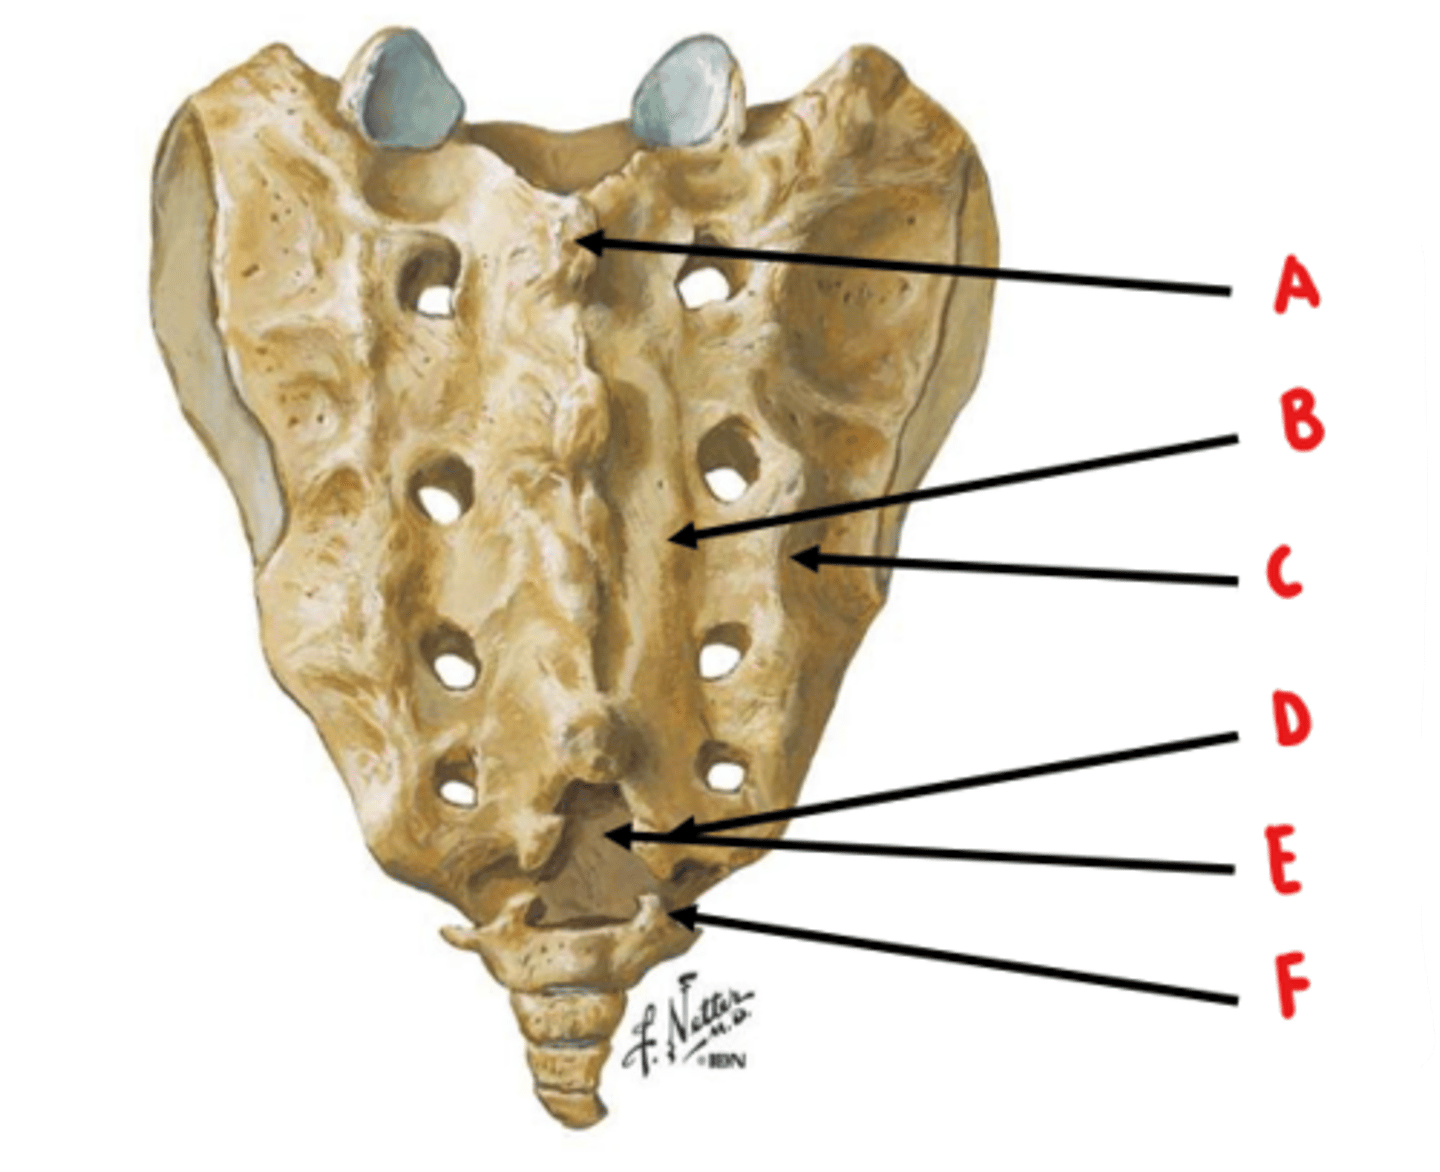

median sacral crest

Identify A

medial sacral crest

Identify B

lateral sacral crest

Identify C

sacral cornua

Identify D

sacral hiatus

Identify E

coccygeal cornua

Identify F

anterior sacral foramen = ventral rami

posterior sacral foramen = dorsal rami

ventral rami are larger because they innervate a larger area of tissue

What structures exit through the anterior and posterior sacral foramen? Which is larger and why?